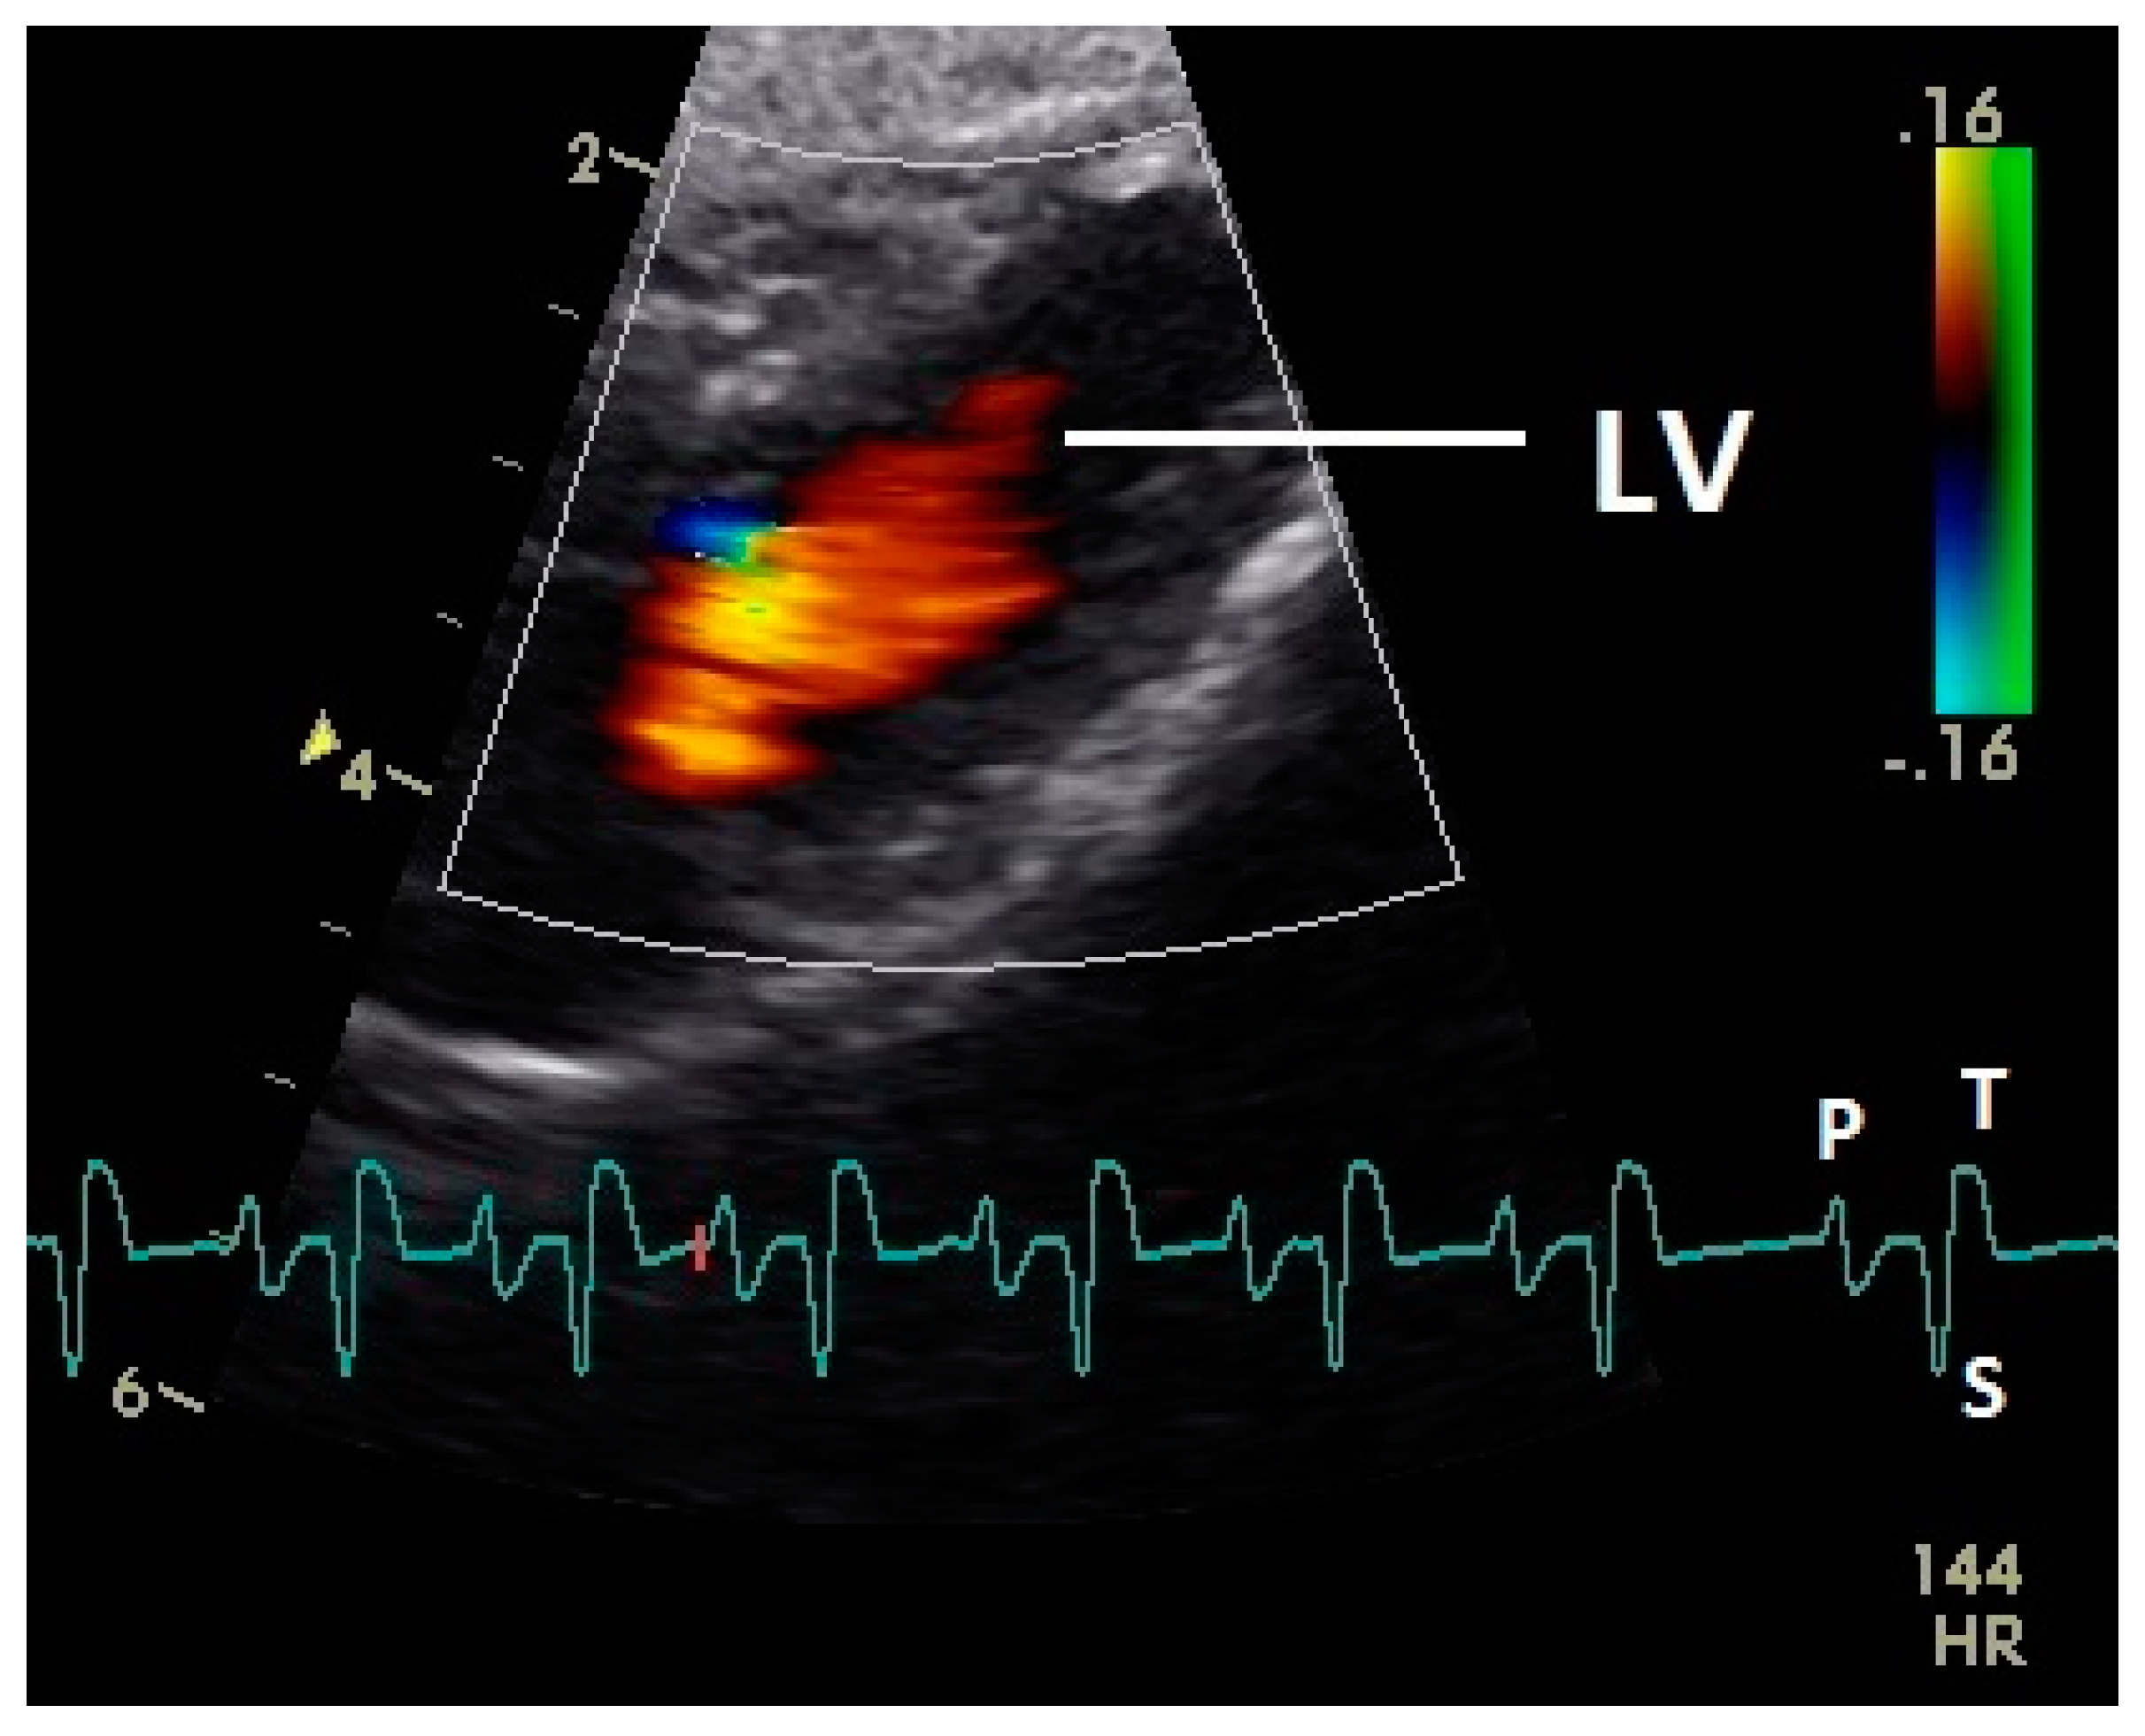

Diastolic ventricular inflow was recorded in the atrium, across the AV valve and within the ventricular inlets and outlets. In the early diastole a red signal was recorded within the left atrium and across the mitral valve annulus into the left ventricle. This phase was interpreted as the passive ventricular filling due to left ventricular relaxation (descending part of T wave in ECG). Behind the longer septal part of the left AV valve leaflet and in the left outflow tract a blue signal in this phase of the cardiac cycle simultaneous to the red signal was observed in 42 birds (97.7%; Figure 1) and in the area of the lateral smaller parts of the left AV valve only in nine birds (20.9%; significant difference Chi-squared test p ≤ 0.001). In the mid diastolic phase in some pigeons the movement of the blood in the ventricle was observed (Figure 2). Within the P wave of the ECG an intense red blood flow signal was evident in the left atrium, crossing the left AV valve and entering the left ventricle as a sign of blood flow caused by atrial contraction. This rapid ventricular filling led to a visible blue signal in the left outflow tract, behind the septal part of the AV valve (97.7%), and in the some pigeons (48.8%; significant difference Chi-squared test p ≤ 0.001) also behind the smaller lateral leaflets of the left AV valve simultaneous to the red signal (Figure 3). In one pigeon the passive diastolic inflow was connected with the active ventricular filling (EA wave).

Figure 1.

Color Doppler image of the early diastolic filling of the left ventricle. The blood inflow in the left ventricle from the atrium (red signal) and vortex formation of the blood flow behind the septal part of the left atrioventricular (AV) valve leaflet and left outflow tract (blue signal) is visible. LV: left ventricle; HR heart rate. Electrocardiogram: P: P wave, S: S wave, T: T wave. The color scale on the right of the image is calibrated in m s−1.